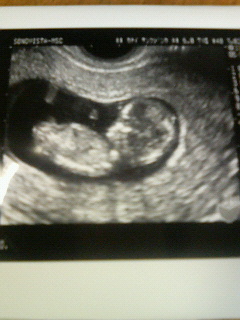

赤ちゃんは4.7センチと、大きくなっていて、両手足もバッチリ見えました。エコーの時、ちょうど赤ちゃんが正面を向いていたので、先生が「これが顔だねぇ」と言ってくれたけど、まるでガイコツみたいで、なんじゃこりゃー??って思いました(^^ゞ

右側が頭、そして体です。うっすら、手足が見えるかな~??

大きくなったでしょ。